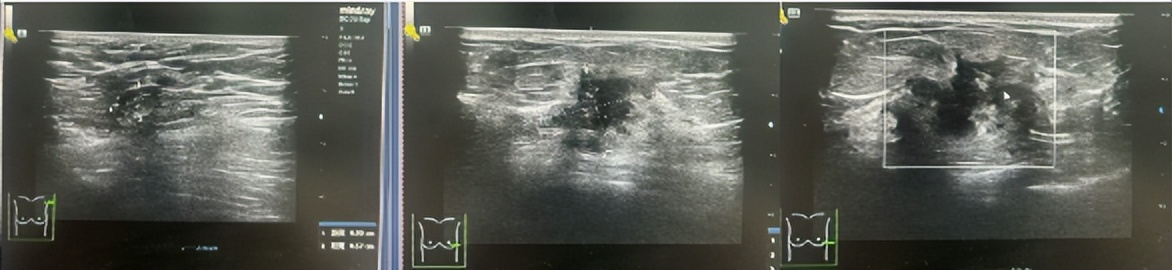

·CT

图4.2023年6月27日CT结果

1、双肺肺气肿并散在肺大疱。

2、双肺多发微小结节,多为磨玻璃结节,密切随诊。

3、左乳外份肿块,建议乳腺相关检查。